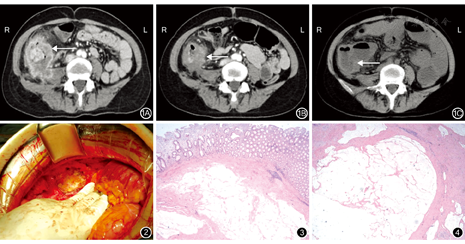

影像科医师:患者CT检查示升结肠及回盲部肠管不规则增厚,呈团块状,最大截面约5.5 cm×5.4 cm,增强不均质强化,病灶左后方与腰大肌分界不清;病灶左前方见大小约0.9 cm×0.8 cm的软组织密度灶,增强环形强化;病灶累及腰大肌及腹壁腹膜,周围肠管轻度扩张水肿,脂肪间隙浑浊,可见数个小淋巴结,较大者大小约0.6 cm×0.5 cm,环形强化。CT检查诊断:升结肠癌并破溃,周围淋巴结转移,腰大肌及腹壁受侵,腹腔脓肿,不全肠梗阻。见图1A。

患者行XELOX方案3周期化疗,同时给予抗炎治疗并改善营养状况。患者第4次入院:一般情况可,偶有腹痛,可耐受,目前有腹胀,感恶心、无呕吐,无发热。饮食差,睡眠可,肛门排气排便减少,近期体质量无明显变化。体格检查:腹部膨隆,有肠型,右季肋区可触及一约6.0 cm×4.0 cm质地坚硬包块,有压痛,无反跳痛,右肾区轻度叩击痛,肠鸣音活跃,移动性浊音阴性。血常规:WBC 8.7×109/L、RBC 4.6×1012/L、Hb 82 g/L、PLT 335×109/L;血清肿瘤标志物:CA125 15.68 U/mL、CA19-9 13.8 U/mL、CEA 6.88 μg/L、AFP 1.87 μg/L;肝功能:ALT 20 U/L、AST 40 U/L、Alb 38 g/L。凝血功能检查未见明显异常、大便常规检查未见明显异常。复查CT:结肠癌化疗后改变,升结肠壁增厚,较前减轻,盆腔多发淋巴结,较前减小;小肠梗阻;盆腔少许积液;肝囊肿。见图1。

李辰生副主任医师:患者经过3个周期的化疗及营养支持治疗,一般情况改善;复查CT示升结肠及回盲部肠管不规则增厚,增强不均质强化,较前范围明显缩小;病灶左前方见大小约0.9 cm×0.7 cm的软组织密度灶,增强环形强化,较前略缩小;病灶累及周围腹膜增厚,周围脂肪间隙较前清晰。右侧腰大肌局部受累,与病灶分界不清晰,范围较前减小。患者目前体质量增加,BMI 20 kg/m2、Alb 39 g/L,达到改善营养状态,使肿瘤降期的目的。

患者完善相关检查后,患者及家属签署手术知情同意书,于2016年12月6日在全身麻醉下行右半结肠癌根治切除+腰大肌部分切除术。术中探查:腹盆腔有明显腹腔积液,肝脾、胃、大网膜、小肠及系膜、腹膜未见明显异常,升结肠肠壁增厚,侵及外膜,小肠明显扩张,升结肠肿瘤约6.0 cm×5.0 cm大小,浸润腰大肌,肠周可见肿大淋巴结(图2)。术后病理学检查结果:右半结肠黏膜慢性炎,近回盲部3.0 cm结肠处黏膜下层、肌层及浆膜面均可见大量黏液湖,仅局灶区域黏液湖内见少量上皮细胞簇,轻-中度异型,考虑黏液腺癌化疗后改变(图3)。"上切线和下切线" 、网膜及阑尾均未查见肿瘤。肠周淋巴结1/13枚查见黏液湖。腹壁包块病理学检查见黏液湖(图4)。免疫组织化学染色检测:角蛋白阴性。术后患者恢复良好,大小便正常。基因检测:BRAF基因错义突变。